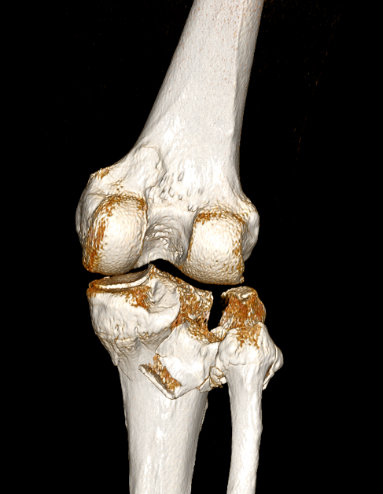

2、图3-6 术前CT见胫骨平台严重塌陷、劈裂

胫骨平台骨折的病人,如果在30年前大多数医院应该会选择保守治疗。那时CT尚未普及,而仅凭X片会低估其损伤的严重程度,容易产生可不必手术的假象,也难以准确判断骨折移位情况。即使想做手术,也没有什么好的内固定可供选用。